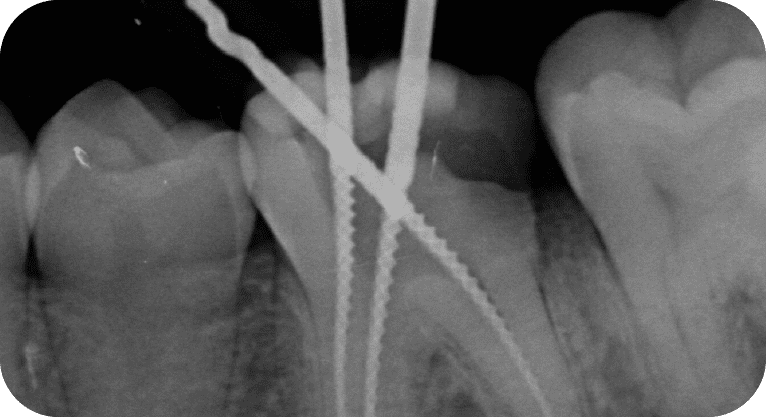

Paciente masculino, “25” años

Tratamiento: Tratamiento de conducto

El paciente presentaba dolor en dos molares por caries profundas. Se realizó endodoncia en ambas piezas, desinfectando y sellando los conductos, seguido de coronas de zirconio para restaurar su función.